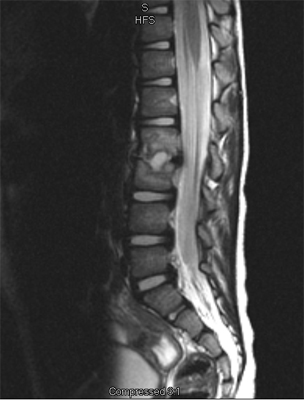

An MRI may be required if further examination of the spine is needed. An MRI machine uses magnetic waves, not X-rays, to show the soft tissues of the body. These tissues include the spinal cord, nerves, and discs. It can also evaluate spinal bones. An MRI allows your healthcare professional to look at slices of the area in question. The test may require the use of dye in an IV. Sedation or anesthesia may be needed to help your child lie still for this test.

A computed tomography (CT) scan may also be ordered. This test is best for evaluating problems with the vertebral bones. Children usually tolerate this test well, however, this test exposes them to radiation, which is significantly higher than during plain x-rays. Sometimes this test may require dye in the spinal canal fluid for easier identification of the spinal cord and nerve root anatomy. When dye is injected for this purpose, the technique is called a myelogram.

In the early stage of the injury an X-ray may not show a fracture. Special imaging tests such as magnetic resonance imaging (MRI), computed tomography scans (CT), or a bone scan may show signs of a stress fracture. Spondylolysis may cause pain in a particular spot in the low back and spasm of the muscles along the spine. Often it will cause pain into the buttocks or thighs. Spondylolysis will often heal with the appropriate rest, a change in activity levels, and by avoiding hyperextension and rotation of the spine. Bracing may be helpful if symptoms do not get better.

Specific back pain means a structural cause for the pain is identifiable. Approximately 25 to 40 percent of children will have specific back pain and will show changes on imaging studies (such as X-ray or magnetic resonance images) that indicate a pathological reason (meaning one caused by disease) for their back pain. These causes include the following: